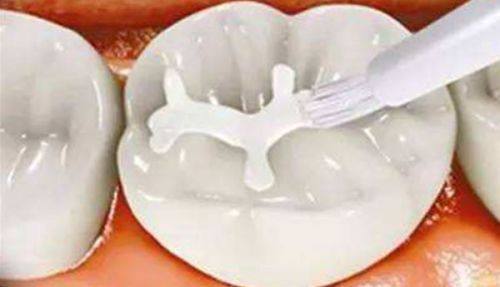

本文围绕“补牙怎么补”介绍了3个关键步骤。补牙前,清理龋坏组织,不同程度龋坏处理方式有别,怕疼可局部麻醉。补牙时,根据牙齿缺损情况选择直接填充、嵌体修复、全冠修复或根管治疗。补牙后,2小时内避免进食,24小时不用患侧嚼硬物,养成良好口腔卫生习惯,定期检查,控制甜食摄入。